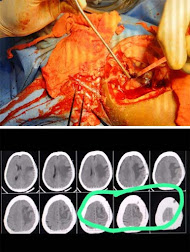

महासमुन्द शहर में ब्रेन ट्यूमर का पहला सफल आपरेशन का दावा, डॉक्टर युगल ने बयान जारी कर दी जानकारी

डॉक्टर युगल चंद्राकर ने मीडिया को बयान जारी कर बताया है कि संकल्प, सेवा

और साधना को समर्पित उनके मल्टी स्पेशलटी

हॉस्पिटल में जहाँ बड़ी से बड़ी चुनौती वाले आपरेशन लगातार किए जा रहे हैं। वहीं,

हाल

ही में ब्रेन ट्यूमर (मस्तिक में गांठ ) का पहली बार महासमुन्द शहर में

सफलतापूर्वक आपरेशन किया गया। कुछ दिन पहले ही एक महिला, सिर में लगातर

दर्द के चलते सोहम हॉस्पिटल में ईलाज हेतु भर्ती हुई। जहाँ ब्रेन की सीटी स्कैन

करने के बाद पता चला कि महिला की सिर में गांठ है। जिसका आपरेशन जरूरी है। सिर का

आपरेशन बहुत ही जटिल प्रक्रिया है। जिसमे आपरेशन के दौरान कभी भी जान हानि का खतरा

और हाथ-पैर में शून्यता की आशंका बनी रहती है।